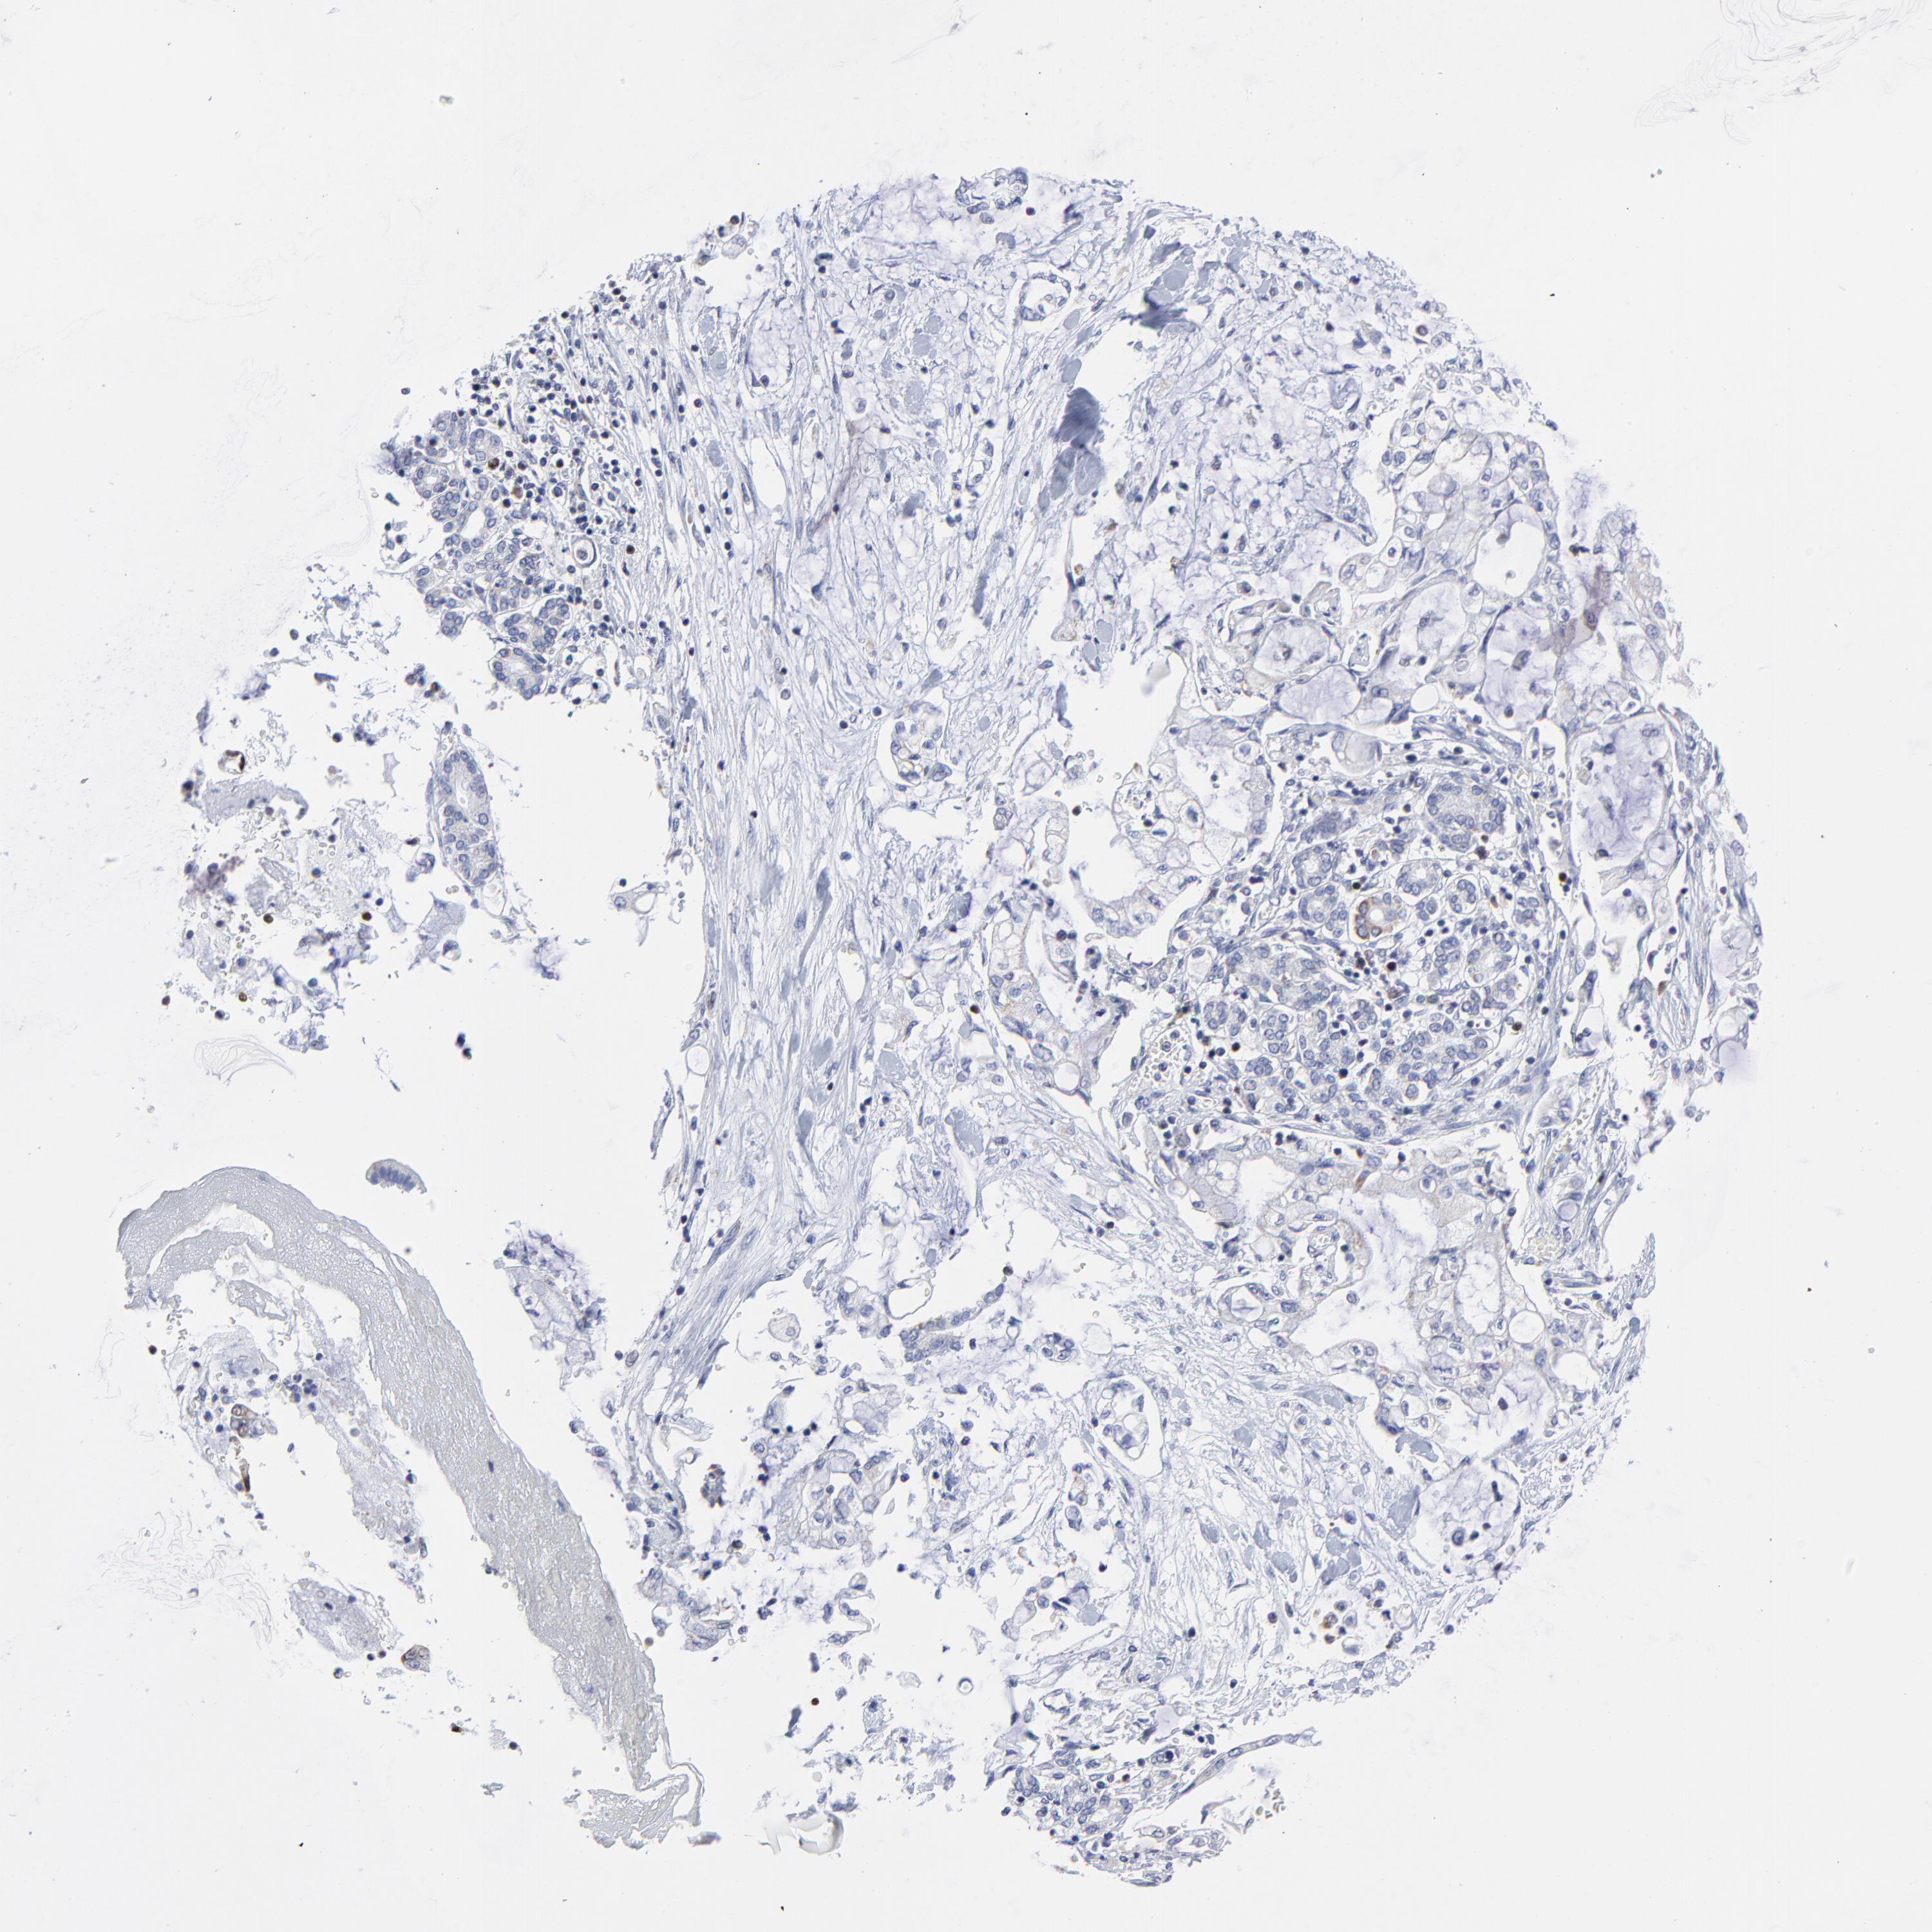

PANCREATIC CANCER - Protein expressioni

A mouse-over function shows sample information and annotation data. Click on an image to view it in a full screen mode. Samples can be filtered based on level of antibody staining by selecting one or several of the following categories: high, medium, low and not detected. The assay and annotation is described here.

Note that samples used for immunohistochemistry by the Human Protein Atlas do not correspond to samples in the TCGA dataset.

Antibody stainingi

Antibody staining in the annotated cell types in the current human tissue is reported as not detected, low, medium, or high, based on conventional immunohistochemistry profiling in selected tissues. This score is based on the combination of the staining intensity and fraction of stained cells.

Each image is clickable and will lead to virtual microscopy that enables deeper exploration of all samples and also displays staining intensity scores, fraction scores and subcellular localization as well as patient and tissue information for each sample.

Antibody HPA002647

Antibody HPA003008

Staining

High

Medium

Low

Not detected

Intensity

Strong

Moderate

Weak

Negative

Quantity

>75%

75%-25%

<25%

None

Location

Nuclear

Cytoplasmic/membranous

Cytoplasmic/membranous,nuclear

Adenocarcinoma, NOS